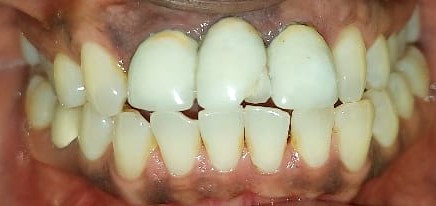

After After